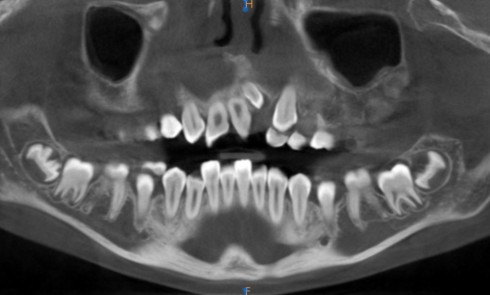

Article réservé à nos abonnés Le flux numérique, un atout pour la prise en charge des patients aux agénésies multiples

Cet article a pour objectif de mettre en avant le traitement d’un patient aux agénésies multiples à l’aide d’outils numériques...